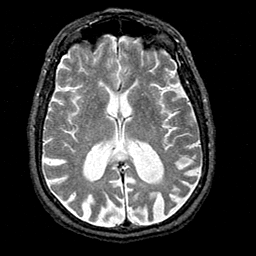

Alzheimer's disease MR T2-weighted -- Slice #26

Tour 1: Next/Previous/Start: At this level, the orbital frontal and superior temporal structures are seen. Note the slight asymmetry of lateral ventricles, with the left posterior portion, sometimes called the atrium, larger than the right. This is a normal variant, and corresponds to the slight asymmetry of the Sylvian fissures. This slight asymmetry can be confirmed by viewing adjacent slices, or by running the spatial movie (choose "cine" next to the sagittal image).